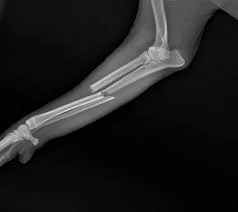

Broken Leg in Dogs: Signs, Causes, and Treatment

Fractures in dogs are a common cause of sudden limping and pain. Learn the symptoms of a broken leg and how veterinarians diagnose and treat bone fractures.